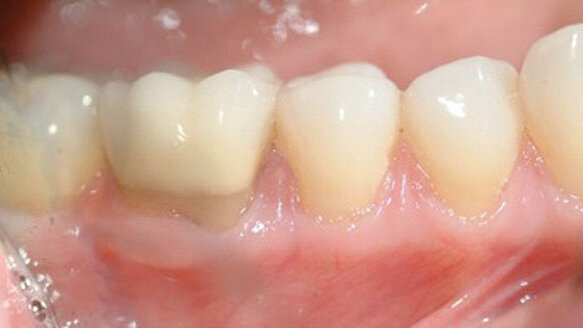

All patients demonstrated surgical results that had an improved and stable zone of attached and keratinized tissues with no evidence of muscle or frenal reattachment compromising the zone of KT. Most often, there was evidence of partial root coverage in Class III Miller recessions. The typical white “scar line” evidenced at the MGJ discussed in Sorrentino and Tarnow’s17 original paper is rarely seen in this one-staged procedure. Patients also found the procedure no more arduous than any other periodontal plastic procedure and, more often then not, the treatment was more comfortable than expected using the Er,Cr:YSGG laser for the initial incision.

The author has done this procedure in more than 100 cases with no untoward results and with great patient satisfaction.

Clinicians all too often are faced with the request: “Can you not do something to cover these teeth?” Many times the concern is not related to sensitivity but rather that of esthetics, after recession has increased over a period of time for a patient on a stable maintenance schedule. Once the periodontal health was assessed to be stable, the remaining compromised zone of KT/AT and the location of the muscle/frenal attachment often appeared to play a role in progressive recession. Thus, the single-staged laser CPF/FGG was developed and completed in more than 100 patients — and was reported to be a comfortable procedure with an esthetic improvement. Additionally, there have even been documented areas of root coverage in Miller III and IV situations and, over the years, some “creeping attachment” has been documented.[36]